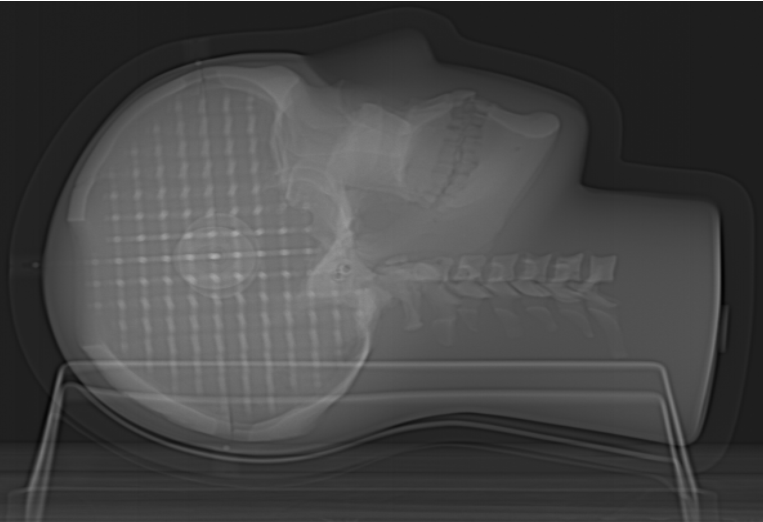

Tissue Equivalent, Anthropomorphic Head

The skull is made from a plastic-based trabecular bone substitute, and the interstitial and surrounding soft tissues are made from a proprietary signal-generating water-based polymer. The entire phantom is encased in a clear plastic shell to protect gel from desiccation. Specially designed pads allow fixation with any stereotactic frame or mounting devices for end-to-end

testing. The phantom is also suitable for frameless SRS QA.

Finely Detailed Inter-Cranial 3D Design

The entire inter-cranial portion of the skull volume is filled with an orthogonal 3D grid of 2.5 mm diameter cross-like shaped rods spaced 10 mm (I-S), 10.5 mm (AP), and 11 mm (L-R). Extra material added in the grid intersections increases grid signal. Five extended axis-rods intersect at the reference origin of the grid. The end of each extended axis is fitted with CT/MR markers allowing for accurate positioning with lasers and co-registration of CT and MR image sets.

The SRS MR Distortion Phantom can be imaged using X-ray, CT and MR. It images well with all MRI sequences tested to date, including T1 weighted, T2 weighted, 3D Time of Flight, MPRAGE and CISS.